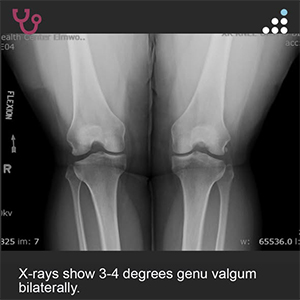

PE: On physical exam, the patient has 3-4 degrees valgus bilaterally. There is a mild effusion about the left knee. ROM of the left knee is 0-130 degrees. There is a normal drawer, pivot shift, and Lachman’s test.